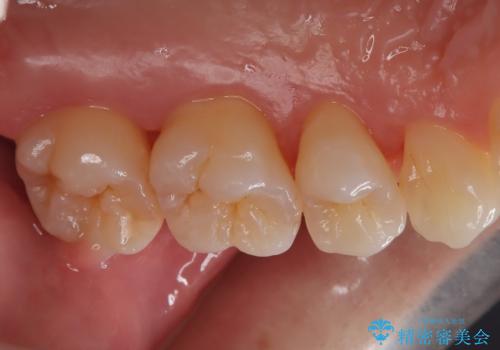

- 定期的にクリーニング(保険適応)に通って頂いている患者さんです。歯周ポケットが4ミリあったため歯茎を開いて歯石を除去するためにオープンフラップ術を行うことにしました。

歯周ポケットがそれほど深くない患者さんでしたが、いざ歯茎を開いてみるとそこにはたくさんの歯石がありました。もし歯周ポケットが4ミリだからと言って放置していれば数年後には、沢山の骨が無くなっていたことが予期出来ます。現段階で歯茎の下にある歯石を除去することにより骨が無くなることを予防する事が出来ました。